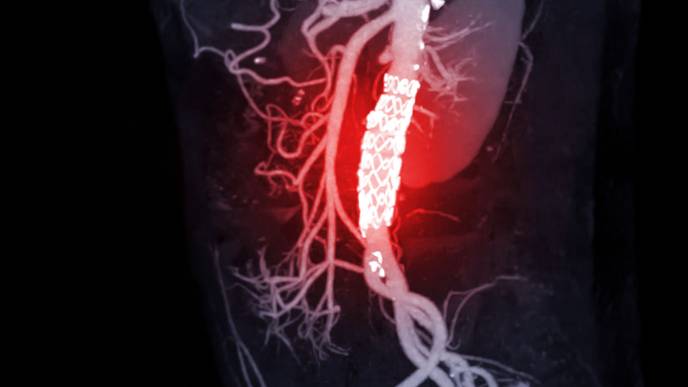

Aortic aneurysms are bulges in the aorta, the largest blood vessel that carries oxygen-rich blood from the heart to the rest of the body. Smoking, high blood pressure, diabetes, or injury can all increase the risk of aneurysms, which tend to occur more often in Caucasian male smokers over the age of 65.

During that period, there is no treatment. Patients are screened regularly via imaging to monitor the rate of the aneurysm's growth. Once it's deemed big enough to potentially rupture (an occurrence that is fatal 90 percent of the time), surgery is the only option. But it's a risky one for elderly patients.